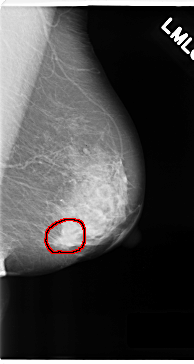

C_0180_1.LEFT_MLO

C_0180_1.LEFT_CC

LEFT_MLO LINES 4720 PIXELS_PER_LINE 2512 BITS_PER_PIXEL 12 RESOLUTION 50 OVERLAY

FILE: C_0180_1.LEFT_MLO.OVERLAY

TOTAL_ABNORMALITIES 1

ABNORMALITY 1

LESION_TYPE MASS SHAPE LOBULATED MARGINS SPICULATED

ASSESSMENT 5

SUBTLETY 5

PATHOLOGY MALIGNANT

TOTAL_OUTLINES 1

BOUNDARY

FILE: C_0180_1.LEFT_CC.OVERLAY